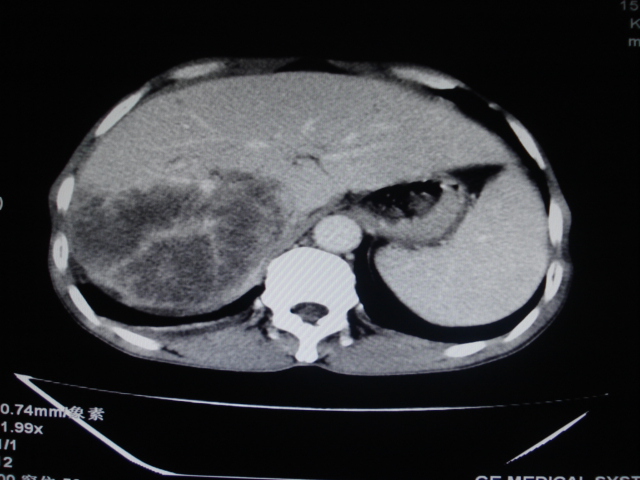

男性,62岁。肝右叶占位,平扫及增强如下,延迟期为15分钟扫描。

给病史及实验室检查!多考虑胆管细胞癌;右肾囊肿。

1)不均匀性脂肪肝。2)肝硬化。3)肝右叶肝癌不排除。4)右肾囊肿。